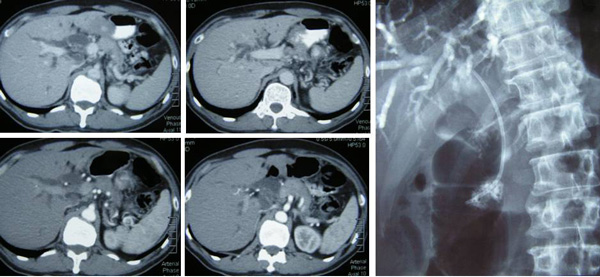

Bak (M952) adalah seorang pria 56 tahun dari Indonesia. Sekitar November 2010, ia mengeluh gatal tapi dia tidak buat apa-apa pun. Pada bulan April 2011, ia pergi buat pemeriksaan di sebuah rumah sakit di Aceh, Sumatera Utara. Dia diberitahu ada tumor di saluran empedu Nya. Pada tanggal 8 April 2011, ia datang kePenanguntuk pemeriksaan lebih lanjut. CT scan perut dan panggul menunjukkan berikut:

• • Sebuah luka hipodens bulat berukuran 10,5 x 21,3 mm terlihat di pertengahan kolon melintang. Dokter tidak yakin apa polip itu?

• Kepala pancreas dan proses uncinate karsinoma dengan distal (duktus bilier umum) obstruksi CBD.

• Hernia inguinoscrotal Kiri.